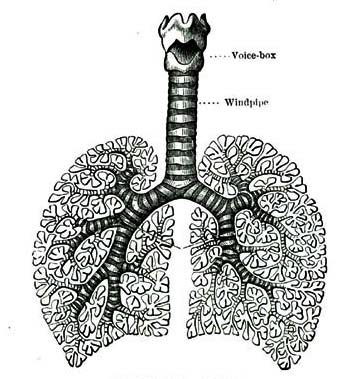

8. The Lungs and Heart.—The chest contains a pair of organs called the lungs, with which we breathe. It also contains something which we can feel beating at the left side. This is the heart. The heart lies between the two lungs, and a little to the left side.

7. The chest contains the two lungs and the heart.

13. The Lungs.—We do not drink air as the frog does, but like the frog we have an air-bag in our bodies. Our air-bag has to be emptied [Pg 67]and filled so often that we cannot live under water long at a time, as a frog does. We call this air-bag the lungs. We have learned before that the lungs are in the chest. We need so much air and have to change the air in our lungs so often that we would not have time to swallow it as a frog does. So nature has made for us a breathing apparatus of such a kind that we can work it like a pair of bellows. Let us now study our breathing-bellows and learn how they do their work.

14. The Windpipe and Air-tubes.—A large tube called the windpipe extends from the root of the tongue down the middle of the chest. The windpipe divides into two main branches, which subdivide again and again, until the finest branches are not larger than a sewing-needle. The branches are called bronchial tubes. At the end of each tube is a cluster of small cavities called air-cells. The air-tubes and air-cells are well shown on the following page.

15. The Voice-box.—If you will place the ends of your fingers upon your throat just above the breast-bone, you will feel the windpipe, and may notice the ridges upon it. These are rings of cartilage, a hard substance commonly called gristle. The purpose of these rings is to keep the windpipe open. Close under the chin you [Pg 68]can find something which feels like a lump, and which moves up and down when you swallow.

This is a little box made of cartilage, called the voice-box, because by means of this curious little apparatus we are able to talk and sing. Two little white bands are stretched across the inside of the voice-box. When we speak, these bands vibrate just as do the strings of the piano. These bands are called the vocal cords.

[Pg 69]16. The Epiglottis.—At the top of the voice-box is placed a curious trap-door which can be shut down so as to close the entrance to the air-passages of the lungs. This little door has a name rather hard to remember. It is called the epiglottis (ep-i-glot'-tis). The cover of the voice-box closes whenever we swallow anything. This keeps food or liquids from entering the air passages. If we eat or drink too fast the voice-box will not have time to close its little door and prevent our being choked. Persons have been choked to death by trying to swallow their food too fast. Do you not think this is a very wonderful door that can open and shut just when it should do so without our thinking anything about it?

17. The Nostrils and the Soft Palate.—The air finds its way to the lungs through the mouth or through the two openings in the nose called the nostrils. From each nostril, three small passages lead backward through the nose. At the back part of the nasal cavity the passages of the two sides of the nose come together in an open space, just behind the soft curtain which hangs down at the back part of the mouth. This curtain is called the soft palate. Through the opening behind this curtain the air passes down into the voice-box and then into the lungs.

[Pg 70]18. The Pleura.—In the chest the air tubes and lung of each side are enclosed in a very thin covering, called the pleura. The cavity of the chest in which the lungs are suspended is also lined by the pleura. A limpid fluid exudes from the pleura which keeps it moist, so that when the two surfaces rub together, as the lungs move, they do not become chafed and irritated.

19. Walls of the Chest.—The ribs form a part of the framework of the chest. The ribs are elastic. The spaces between them are filled up with muscles, some of which draw the ribs together, while others draw them apart. Can you tell any reason why the walls of the chest are elastic? The lower wall or floor of the chest cavity is formed by a muscle called the diaphragm, which divides the trunk into two cavities, the chest and the abdomen.

20. How we Use the Lungs.—Now let us notice how we use the lungs and what takes place in them. When we use a pair of bellows, we take hold of the handles and draw them apart. The sides of the bellows are drawn apart so that there is more room between the sides. The air then rushes in to fill the space. When the bellows are full, we press the handles together and the air is forced out.

21. It is in just this way that we breathe.[Pg 71] When we are about to take a long breath, the muscles pull upon the sides of the chest in such a way as to draw them apart. At the same time the diaphragm draws itself downward. By these means, the cavity of the chest is made larger and air rushes in through the nose or mouth to fill the space. When the muscles stop pulling, the walls of the chest fall back again to their usual position and the diaphragm rises. The cavity of the chest then becomes smaller and the air is forced out through the nose or mouth. This process is repeated every time we breathe.

22. We breathe once for each four heart-beats. Small children breathe more rapidly than grown persons. We usually breathe about eighteen or twenty times in a minute.

23. How Much the Lungs Hold.—Every time we breathe, we take into our lungs about two thirds of a pint of air and breathe out the same quantity. Our lungs hold, however, very much more than this amount. A man, after he has taken a full breath, can breathe out a gallon of air, or more than ten times the usual amount. After he has breathed out all he can, there is still almost half a gallon of air in his lungs which he cannot breathe out. So you see the lungs hold almost a gallon and a half of air.

[Pg 72]24. Do you think you can tell why Nature has given us so much more room in the lungs than we ordinarily use in breathing? If you will run up and down stairs three or four times you will see why we need this extra lung-room. It is because when we exercise vigorously the heart works very much faster and beats harder, and we must breathe much faster and fuller to enable the lungs to purify the blood as fast as the heart pumps it into them.

25. The Two Breaths.—We have learned that the air which we breathe out contains something which is not found in the air which we breathe in. This is carbonic-acid gas. How many of you remember how we found this out? We can also tell this in another way. If we put a candle down in a wide jar it will burn for some time. If we breathe into the jar first, however, the candle will go out as soon as we put it into the jar. This shows that the air which we breathe out contains something which will put a candle out. This is carbonic-acid gas, which is a poison and will destroy life.

26. Other Poisons.—The air which we breathe out also contains other invisible poisons which are very much worse than the carbonic-acid gas. These poisons make the air of a crowded or unventilated room smell very unpleasant to one [Pg 73]who has just come in from the fresh air. Such air is unfit to breathe.

27. The Lungs Purify the Blood.—We have learned that the blood becomes dark in its journey through the body. This is because it loses its oxygen and receives carbonic-acid gas. While passing through the capillaries of the lungs, the blood gives out the carbonic-acid gas which it has gathered up in the tissues, and takes up a new supply of oxygen, which restores its scarlet hue.

28. How the Air is Purified.—Perhaps it occurs to you that with so many people and animals breathing all the while, the air would after a time become so filled with carbonic-acid gas that it would be unfit to breathe. This is prevented by a wonderful arrangement of Nature. The carbonic-acid gas which is so poisonous to us is one of the most necessary foods for plants. Plants take in carbonic-acid gas through their leaves, and send the oxygen back into the air ready for us to use again.

29. We have already learned that the oxygen taken in by the lungs is carried to the various parts of the body by the little blood corpuscles. The effect of strong liquors is to injure these corpuscles so that they cannot carry so much oxygen as they ought to do. For this reason, the blood of a drunkard is darker in color than [Pg 74]that of a temperate person, and contains more carbonic-acid gas. The drunkard's lungs may supply all the air he needs, but his blood has been so damaged that he cannot use it. Excessive smoking has a similar effect.

1. Our bodies need air, just as a candle or a fire does.

2. A small animal shut up in a close jar soon dies for want of air. We need the oxygen which the air contains.

3. Oxygen causes a sort of burning in our bodies.

4. The burning in our bodies keeps us warm, and destroys some of the waste matters.

5. The breathing organs are the windpipe and bronchial tubes, the voice-box, the epiglottis, the nostrils, the soft palate, the lungs, the air-cells, the pleura, the diaphragm, and the chest walls.

6. When we breathe we use our lungs like a pair of bellows.